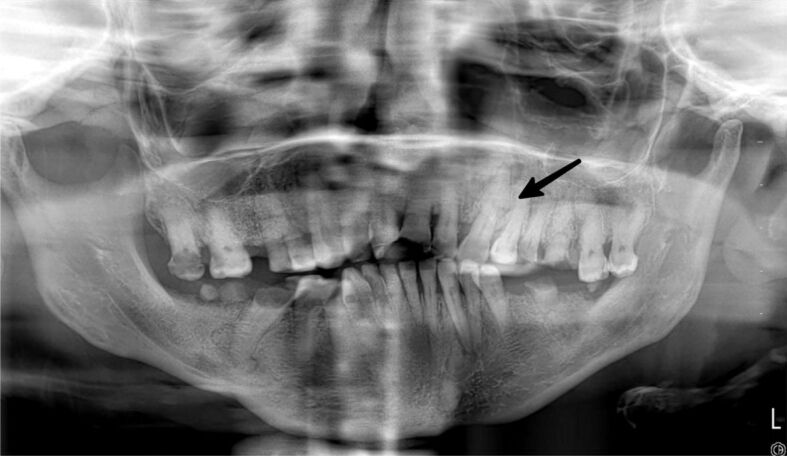

Peripheral ossifying fibroma (POF) is a reactive, benign gingival enlargement. Its etiology is not fully known. It can be seen in many different sizes in the mouth. The histopathological appearance of POF is mineralized tissue and fibrous proliferation. All relevant soft and hard tissues must be removed to prevent recurrence. Periodontal tissue remaining after excision is important for tooth preservation. With large lesions, the loss of healthy periodontal tissue is also large. Periodontal surgical approaches are important to preserve the remaining periodontal tissue. The positive effects of autogenously obtained titanium-prepared platelet-rich fibrin (T-PRF) and connective tissue graft (CTG) on soft tissue are well known. A 34-year-old woman presented with a fibrous and pedunculated gingival mass in the upper left canine premolar region. The operation was performed with complete excision of the lesion down to the bone along with the surrounding healthy tissue. Periodontal treatment of the large defect created after excision of a large POF lesion was performed with laterally positioned flap, CTG and T-PRF. The periodontal tissue and defect were noted to heal in a healthy manner at the 6-month follow-up. POF is a benign lesion; however, it has a high recurrence rate. Complete elimination of the lesion is crucial to prevent recurrence. Periodontal surgical methods and biomaterials applied after surgical excision are significant to maintain the periodontal health of the remaining teeth and tissues.